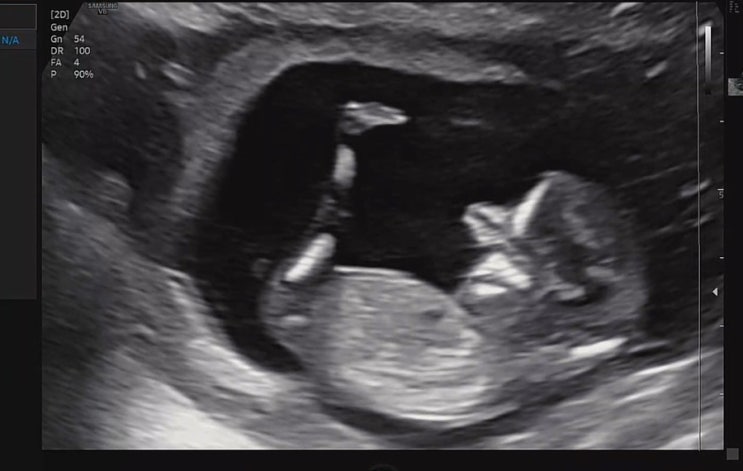

임신일기-23,24주 공포의 임당검사 재검 당첨

역류성 식도염이 너무 심해 도저히 안되겠다하고 영양제를 끊었다. 의사와 상담한 건 아니고 중학교때부터 ...